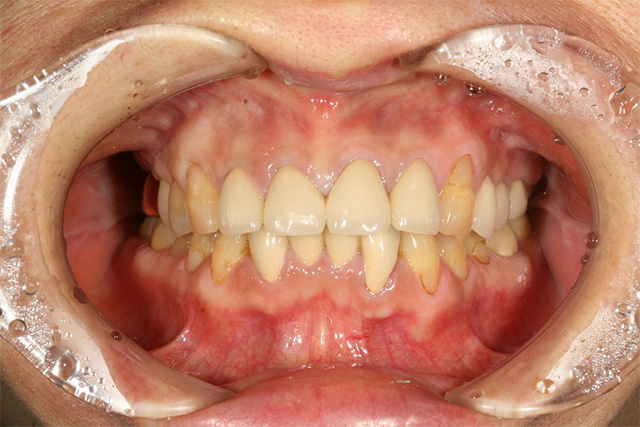

審美症例